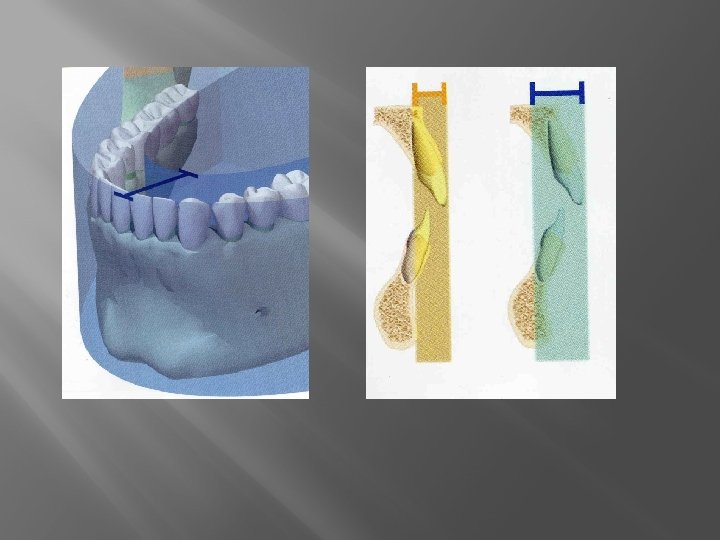

Ami a Pacienst, az a személyzetet is védi � � � Indokolt legyen a felvétel A felvételt készítő személy gyakorlott legyen, ne ismételjen A választott technika legyen: � � � � � gyorsan elvégezhető legkisebb sugárterhelésű célirányos archiválható Filmtartó Fejtámlás szék Érzékeny film – digitalis radiográfia A paciens szellemi és anatómiai korlátainak ismerete Ólomkötény Megfelelő geometriájú tubus alkalmazása

Eszközpark El kell dönteni: � Melyik számunkra a legideálisabb röntgengép � Mi a célunk: � Lehető legalacsonyabb sugárterhelés � Lehető legjobb minőségű kép � � A modern eszközök kevesebb szórt sugárzással jellemezhetők Hogyan segít a digitális rendszer?